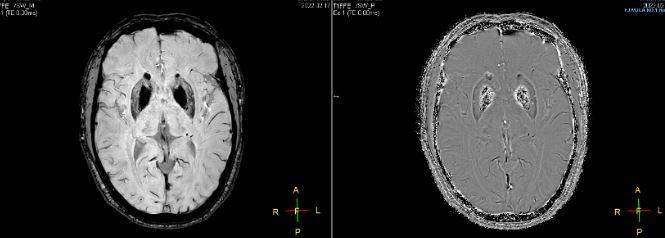

双侧苍白球可见t1wi高信号,t2wi高信号区域,无占位效应.

呈均质较高密度,轻者钙化仅局限于苍白球,尾状核,壳核和丘脑,严重者

以苍白球钙化最常见.可同时见于尾状核和丘脑.